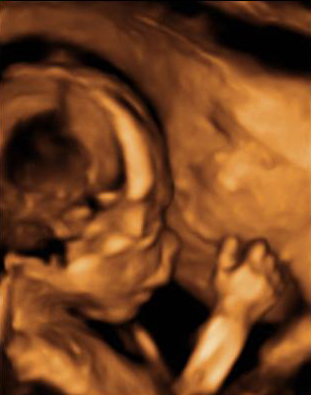

La imagen del ultrasonido muestra un feto de 19 semanas y 4 días de gestación con la mano cerca de la cara.

La mano del feto se aproxima a la cara